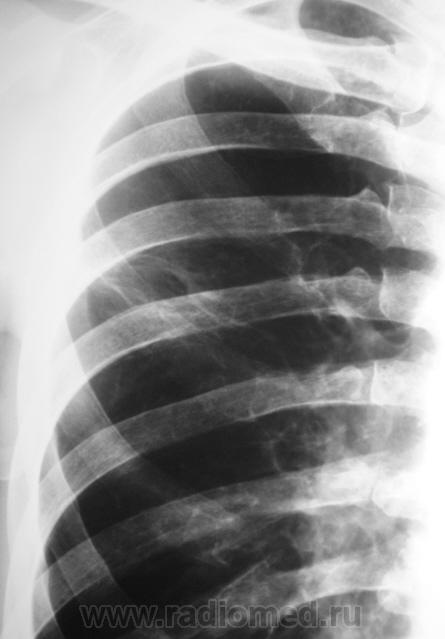

Пациент явился со "своим" снимком и с диагнозом..."Центральный рак левого лёгкого".

Может если не пнемония, то вполне и туберкулез, т.б похоже архивчик имеется..

Это из тех случаев где по одному снимку очень тяжело формировать диагноз. Уверен больному и бок и томограммы досняли.

Такое впечатление что там полостюха имеется..

Вы про какую сторону? Справа действительно похоже, но без томограмм утверждать нельзя.

Почемуто видиться распад слева..., ну или там неплотный узел какой с перифокальным восполением..

Слева очень не уверен, дообследование. А справа, мне кажется, на кисту похоже, но нужны tg, может быть просто сочетание теней.

Да.. справа или полостюшка или суммация теней.. Ждемс)))

напоминает абсцедирующую пневмонию.

Инф туберкулез с распадом7

Получается видимо каверна справа засеяла левое легкое - похоже реальный клиент фтизиатора и отличный пример невовремя пройденной флюорографии.

Пацитента с большим удовольствием забрали фтизиатры.